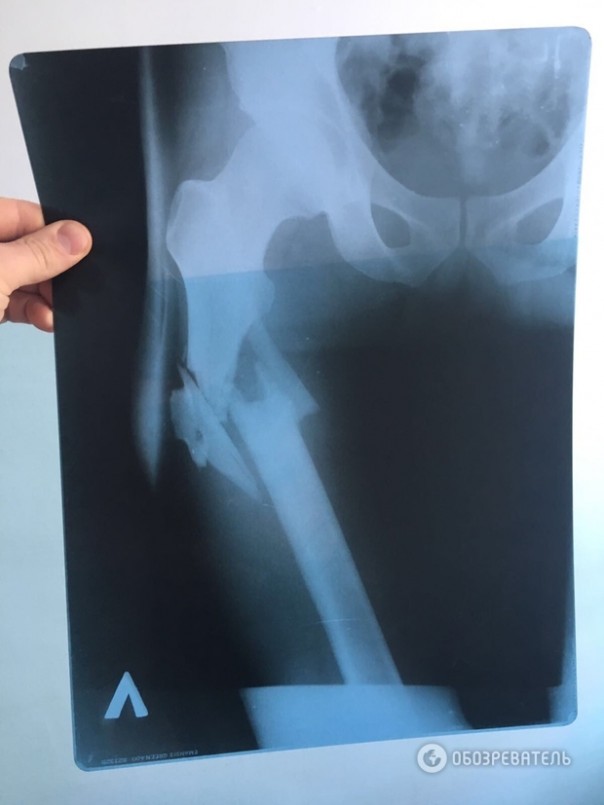

Напомним, "Обозревателю" удалось заполучить также рентгеновский снимок простреленной ноги Химикуса и заснять пулевые отверстия на его штанах. Учитывая положение входного и выходного отверстий от пули, можно предположить, что пуля "шла" сверху вниз.

Врач, оперировавший Вячеслава Химикуса, которого ранил из пистолета народный депутат Сергей Пашинский, на допросе подтвердил, что на месте перелома у пострадавшего обломки кости смещены вниз от таза. Об этом "Обозревателю" сообщил собственный источник.

Он также подчеркнул, что данный факт подтверждает, что Пашинский выстрелил сверху в ногу Химикусу, а не из положения лежа, как нардеп утверждал ранее.